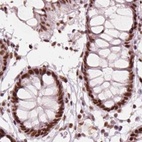

Immunohistochemical staining of human cerebral cortex, gastrointestinal, placenta and testis using Anti-ELF2 antibody HPA071166 (A) shows similar protein distribution across tissues to independent antibody HPA006057 (B).